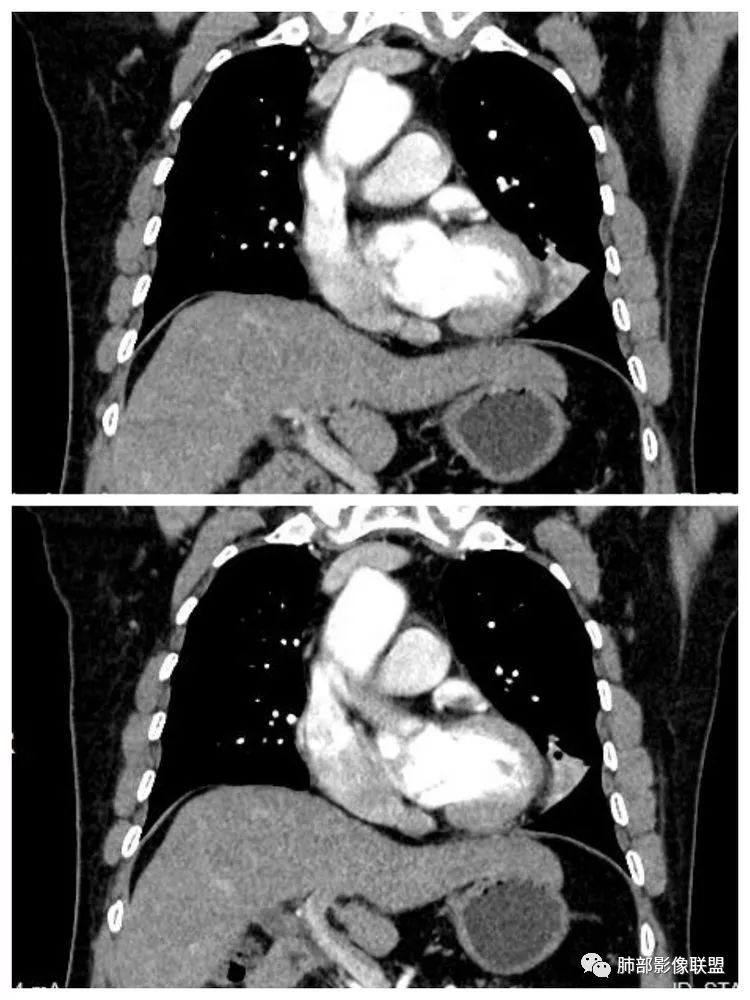

患者,男 ,66岁, “左肺占位”收住院。CEA 5.23 轻度增高 医学百科网 | YxBaike.Com

平扫 动脉期 静脉期 40HU、48HU、57HU

患者老年男性,“左肺占位”收入住院。查CEA轻度升高。胸部CT:左肺肺门占位并左肺下叶阻塞性,远端肺组织膨胀不全,增强可见轻度强化,内似见低密度灶。双肺多发类圆形结节,以左肺上叶尖后段为大,内可见部分钙化,边缘光滑、清楚。综合考虑恶性病变,鳞癌并转移可能大,鉴别腺癌、结核。

胸CT:左下叶内前基底段肿块,支气管堵塞,强化弱,延迟强化,两肺多处结节,右上肺门淋巴结大。常规考虑:肺癌可能 ,肺内小结节,转移?鉴别:错构瘤,TB等。 医学百科网 | YxBaike.Com

1.定位:左肺块影同时累及下舌段及下叶内基底段且相互延续。病灶跨叶,或存在叶裂发育异常,或者说就是病灶的肺门蔓延。 医学百科网 | YxBaike.Com

2.病灶前上部分与舌段支气管相关且形成阻塞。

3.左肺上叶另见孤立结节影,边界清楚光整,中央钙化,未见脂质密度特征。 医学百科网 | YxBaike.Com

4.增强扫描左肺门区块影轻度强化,强化程度轻于舌段周围不张肺组织。

左肺上叶孤立小结节影未见异常强化。 医学百科网 | YxBaike.Com

5.双肺门及纵隔未见明确增大淋巴结。

6.分析:男性患者,左肺门区块状影,支气管阻塞,强化不显著,未见淋巴结肿大,更多见于肺鳞癌。难以解释的是下肺病灶的生长方式。 医学百科网 | YxBaike.Com

沿肺门或是叶裂缺损孤立发生且蔓延,转移性腺癌似乎可以解释,但占据较大支气管腔就属罕见了。 医学百科网 | YxBaike.Com